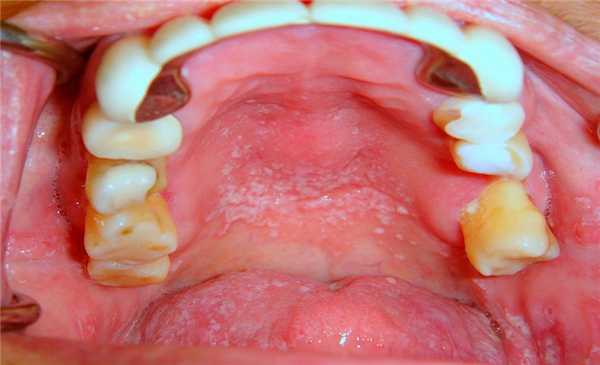

Без надлежащего слюноотделения и в условиях нарушенного уровня рН ротовой полости, ее пространство быстро колонизируется кариесогенными микроорганизмами, которые являются основным патологическим фактором развития поражений твердых тканей зубов. Что же касается связи между ксеростомией и заболеваниями пародонта, то данные литературы в этом плане весьма противоречивы. Некоторые исследователи обнаружили, что пародонтологический статус пациентов с синдромом Шегрена аналогичен таковому у пациентов группы контроля, другие же наоборот – утверждают о худшем состоянии тканей пародонта у пациентов с ксеростомией. Последние аргументируют повышенный риск поражения пародонта увеличенным формированием зубного налета вследствие дефицита слюны. Кроме того, недостаток слюны значительно повышает риск возникновения грибковой инфекции в полости рта, особенно кандидоза, не говоря уже о том, что у большинства пациентов с ксеростомией наблюдаются признаки углового хейлита и атрофия сосочков языка. Будучи сильно связанными с изменениями микрофлоры ротовой полости, такие состояния обуславливаются в первую очередь грибами рода кандида, которые присутствуют в ротовой полости, на коже и в кишечнике. Взаимодействие с белками слюны частично помогает организму контролировать колонизацию грибов рода Candida в полости рта. Микрофлора ротовой полости может изменяться, что приводит к прогрессивному увеличению количества не только оппортунистических, но и патологических бактериальных агентов (фото 2).

Фото 2. Псевдомембранозный кандидозный стоматит у пациента с ксеростомией.